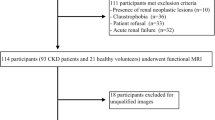

Fifty-two patients (29 men, 23 women; mean age, 36 years; age range 18–62 years) were successfully included from October 1, 2011 to December 31, 2012. Patients were included if they met the following criteria: (a) met clinical diagnostic criteria for CKD; (b) had renal pathology by renal biopsy; (c) had no other medical diagnosis that may affect renal function, such as gout, diabetes, or hypertension; and (d) had magnetic resonance imaging (MRI) with DWI 2–10 days prior to renal biopsy. Patients were excluded if the exhibited any of the following: (a) they could not tolerate MRI examination; (b) the image quality did not meet requirements of the study; (c) there were malignant or multiple benign renal masses that could affect data analysis; or (d) if renal biopsy could not be performed. Eight patients were excluded because of these exclusion criteria.